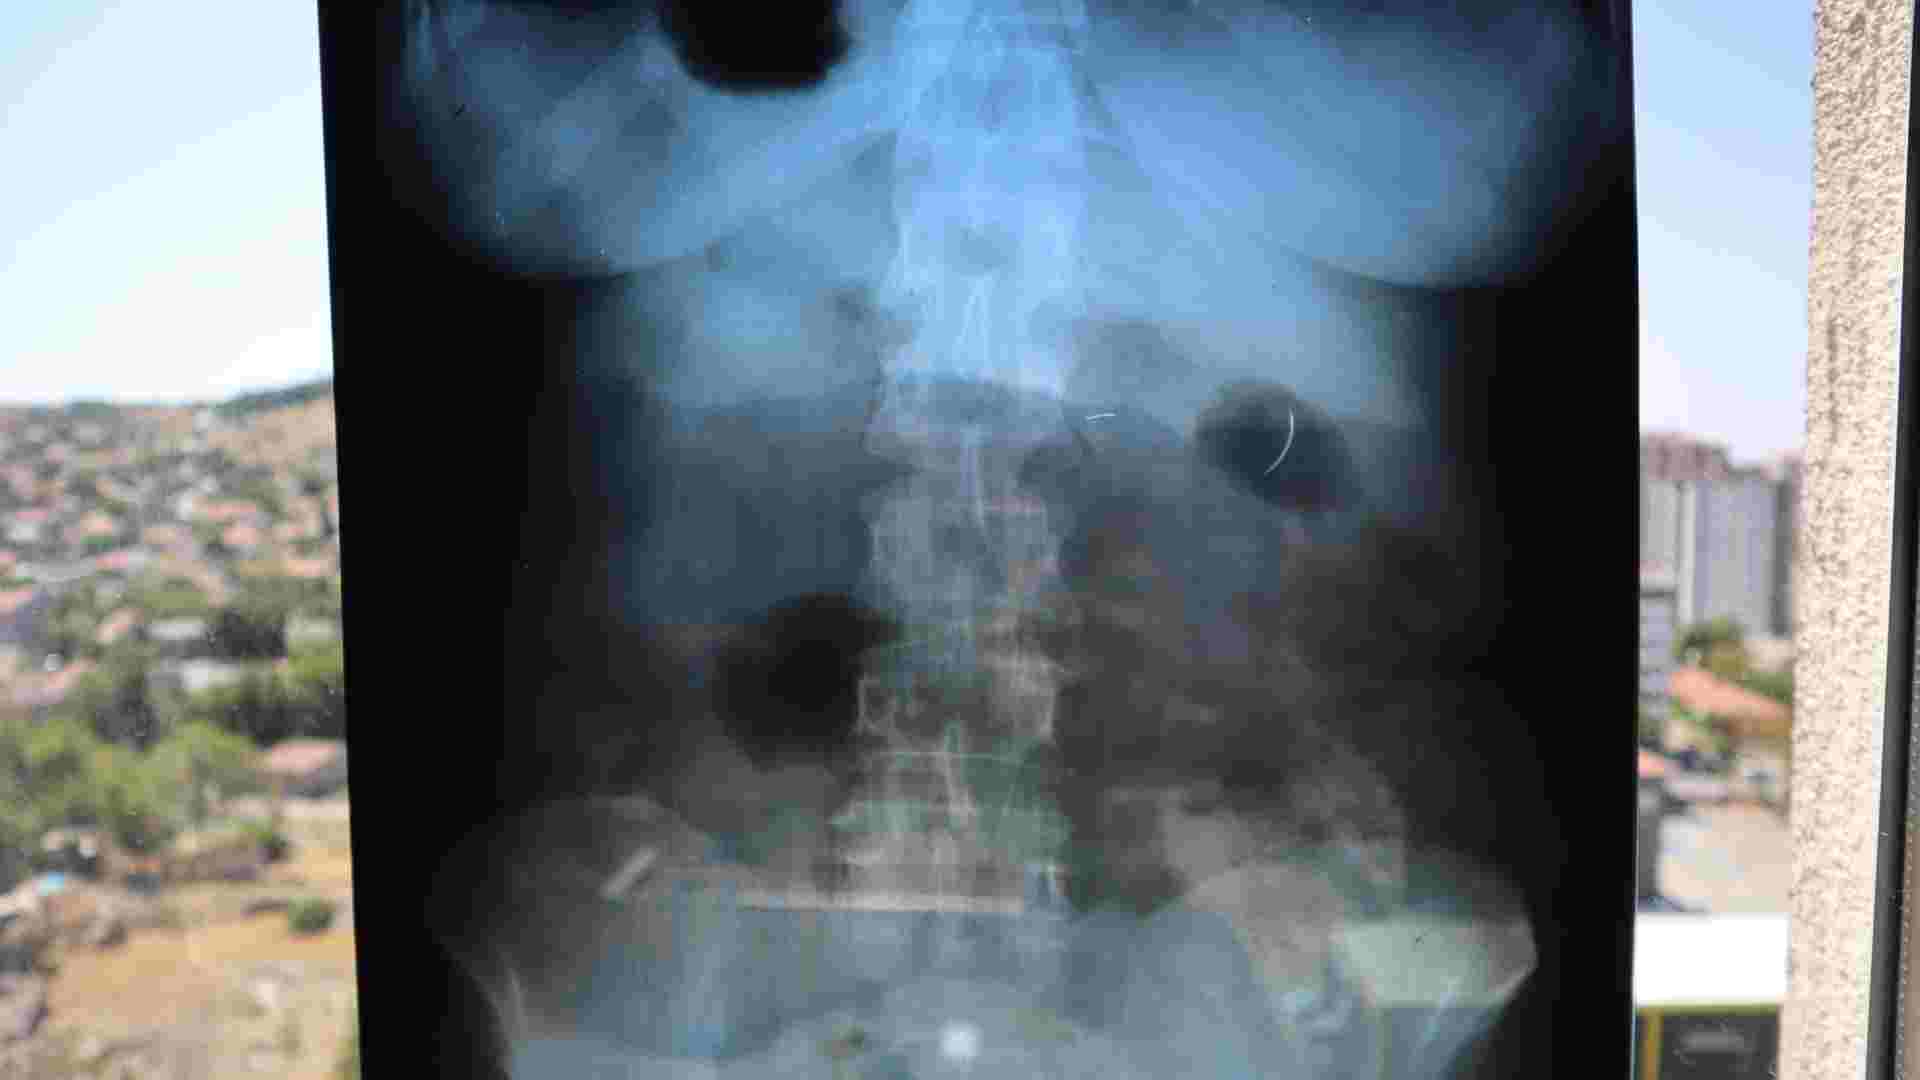

İki çocuk annesi Ayhan Tanyıldız, 2003 yılında karaciğerindeki kist nedeniyle ameliyat oldu. Ameliyattan 6 yıl sonra böbrek rahatsızlığı şikayetiyle gittiği hastanede çekilen röntgende karnında ameliyat iğnesi olduğu tespit edildi. MR cihazına girmesi sakıncalı bulunan Tanyıldız, kist ameliyatını gerçekleştiren doktor hakkında dava açtı.

Yaklaşık 19 yıl süren yargı sürecinin ardından Tanyıldız, maddi tazminat almaya hak kazandı. Ancak karnındaki iğne, riskli olduğu gerekçesiyle hala çıkarılamadı.